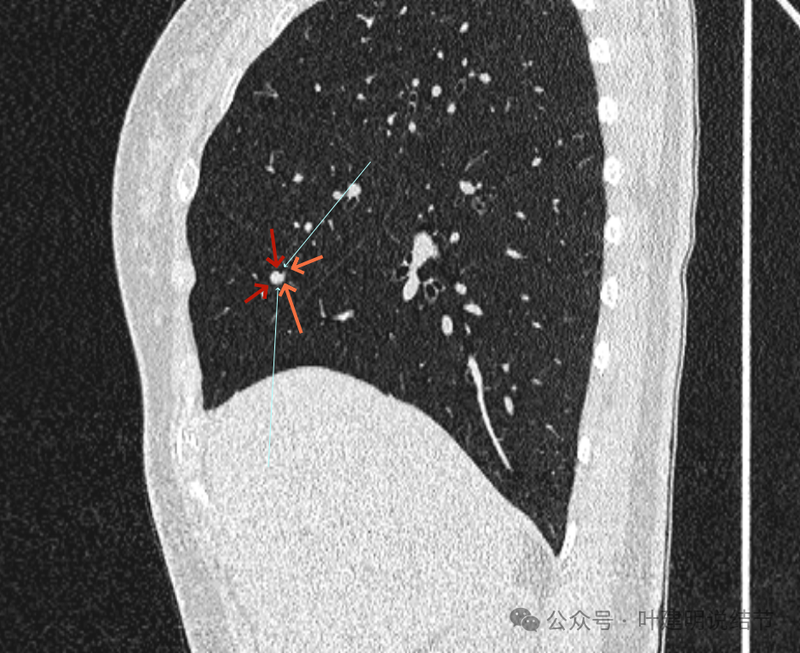

病赤与血管在蓝色箭头处失去间隙,像是侵蚀血管壁,造成血管受侵犯破坏。病灶是软组织密度的,而且整体看有膨胀感。

病灶密度稍不均。表面不光滑。

病灶与边上血管间隙不清。

桔色箭头所示的血管受压稍有移位。

密度不同,关系密切。

边缘区域也是有膨胀感。